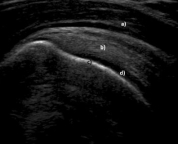

-Refer to the figure. What are the structures marked a-d in this normal longitudinal ultrasound of the shoulder?

D) (a) deltoid muscle, (b) supraspinatus tendon, (c) cortical bone, (d) articular cartilage

(a) deltoid muscle, (b) supraspinatus tendon, (c) cortical bone, (d) articular cartilage